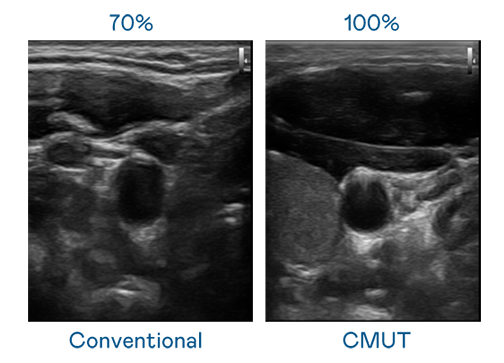

CMUT 技術是一種用電容式微機電元件來產生超音波訊號的技術。與傳統 PZT 壓電式技術相比,CMUT 頻寬增加 30%,更寬頻的超音波訊號讓影像解析度大幅提升,是實現高影像品質醫療超音波掃描、促進精準醫療發展的關鍵技術。

超音波影像的解析度高低,首先取決於探頭能發出的訊號頻寬。z6com·尊龙时凯 CMUT 可提供高清晰的超音波訊號,提供高頻寬、高靈敏度、影像紋理細節更高的超音波影像,協助醫護人員縮短影像判讀時間及利用精準的醫療影像進行診斷。